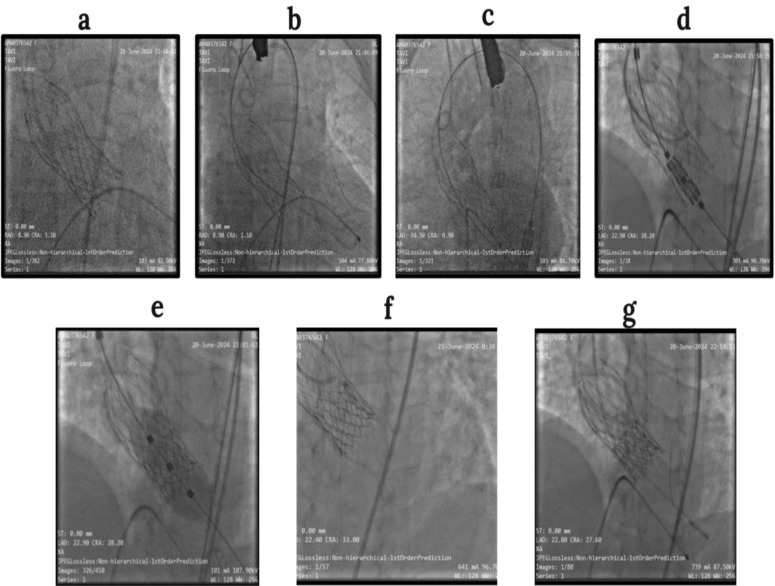

Case presentation: We report the case of a 68-year-old female patient of Indian ethnicity with prior transcatheter aortic valve implantation using a 26 mm CoreValve (Medtronic), presenting with symptomatic valve degeneration. Her case having been deemed high-risk for open surgical intervention, she was selected for a transcatheter aortic valve implantation-in-transcatheter aortic valve implantation procedure. Preprocedural computed tomography imaging showed a critical risk plane for the left main coronary artery, necessitating coronary protection. A 23 mm balloon-expandable Myval transcatheter heart valve was implanted using transfemoral access. Coronary protection was initiated with prepositioning of a coronary guidewire in the left coronary artery. Following valve deployment, the patient developed hypotension with left main coronary artery flow compromise, requiring bailout left main coronary artery stenting, resulting in a chimney configuration. Postdeployment angiography confirmed optimal valve positioning with preserved coronary flow. The patient initially developed hypotension and severe hypokinesia, which was managed successfully with emergency left main coronary artery stenting and supportive care. She exhibited immediate hemodynamic recovery and was discharged in a stable condition. This is the first documented case of a Myval-based transcatheter aortic valve implantation-in-transcatheter aortic valve implantation with left main coronary artery chimney stenting from East India.